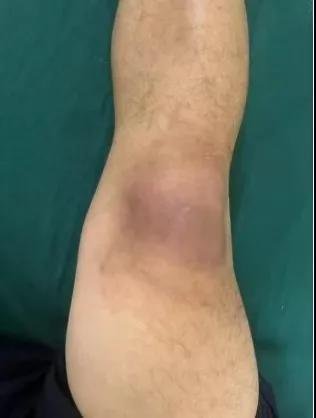

近日,漯河醫(yī)專二附院(漯河市骨科醫(yī)院、漯河市立醫(yī)院)手顯微外科(骨四科)李俊明主任團(tuán)隊(duì)?wèi)?yīng)用清熱解毒、拔毒生肌類中藥(骨炎膏)外用結(jié)合抗生素成功治愈一例膝關(guān)節(jié)外傷后軟組織感染病人。

患者,以“外傷致右膝紅腫、疼痛20余天”為主訴就診,20余天前,因騎電車摔傷右膝關(guān)節(jié),致使出現(xiàn)右膝腫脹、疼痛、活動受限,在當(dāng)?shù)蒯t(yī)院給予消腫、止痛治療效果差,繼而出現(xiàn)膝關(guān)節(jié)紅腫熱痛癥狀,門診給予滑膜炎片及消腫止痛藥物治療癥狀未見好轉(zhuǎn),慕名前來我院手顯微外科住院。入院當(dāng)天即給予中藥外敷(骨炎膏),穿刺膿性分泌物送細(xì)菌培養(yǎng),給予廣譜抗生素治療(細(xì)菌培養(yǎng)未出)。

中藥外敷(骨炎膏)主要適用于局部紅腫熱痛,四肢血栓形成、靜脈炎等,具有清熱解毒,拔毒生肌的作用。

中藥外敷骨炎膏給藥直接作用于病灶,彌補(bǔ)了單純口服藥物局部濃度不足的缺陷;同時,中藥外敷與抗生素的系統(tǒng)性抗感染形成"靶向-全身"雙重干預(yù),可顯著縮短療程并降低耐藥風(fēng)險,更為中西醫(yī)結(jié)合治療軟組織感染提供新的思路。(盧 闖 賈煒煒 劉 旭 袁錦鈺)